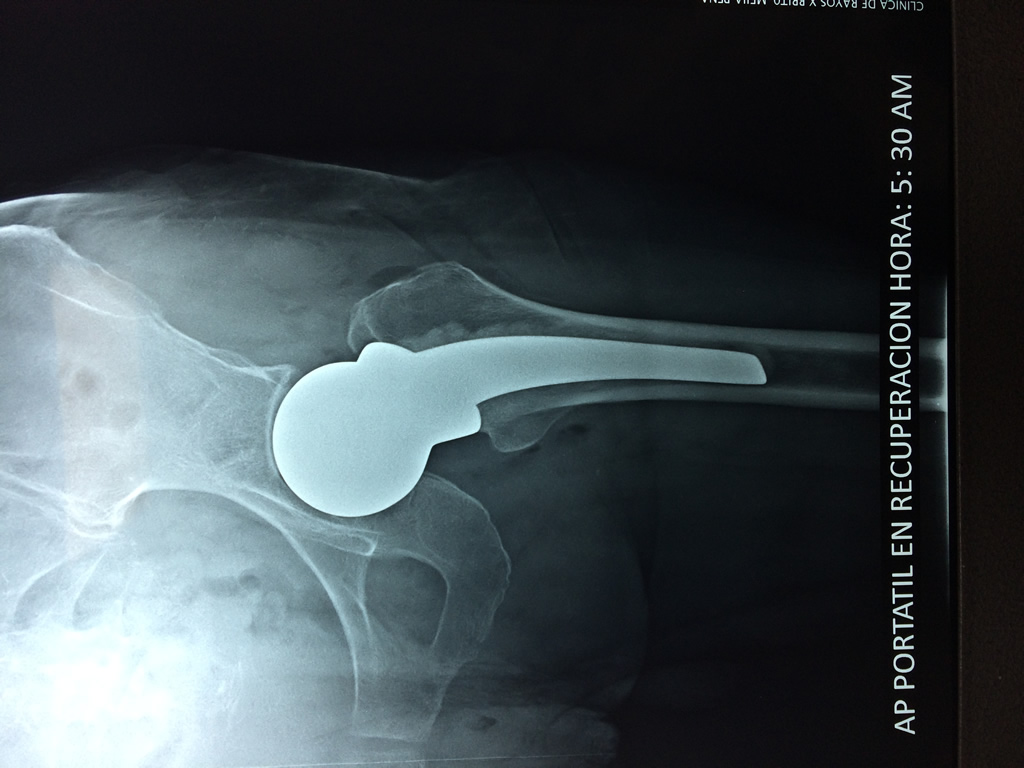

Cirugías de Hombros - Cadera

La cirugía de fractura de cadera se realiza para reparar una ruptura en la parte superior del hueso del muslo. Este hueso se denomina fémur.

Es parte de la articulación coxofemoral. Si una fractura de cadera no recibe tratamiento, es posible que deba permanecer en una silla o en la cama.